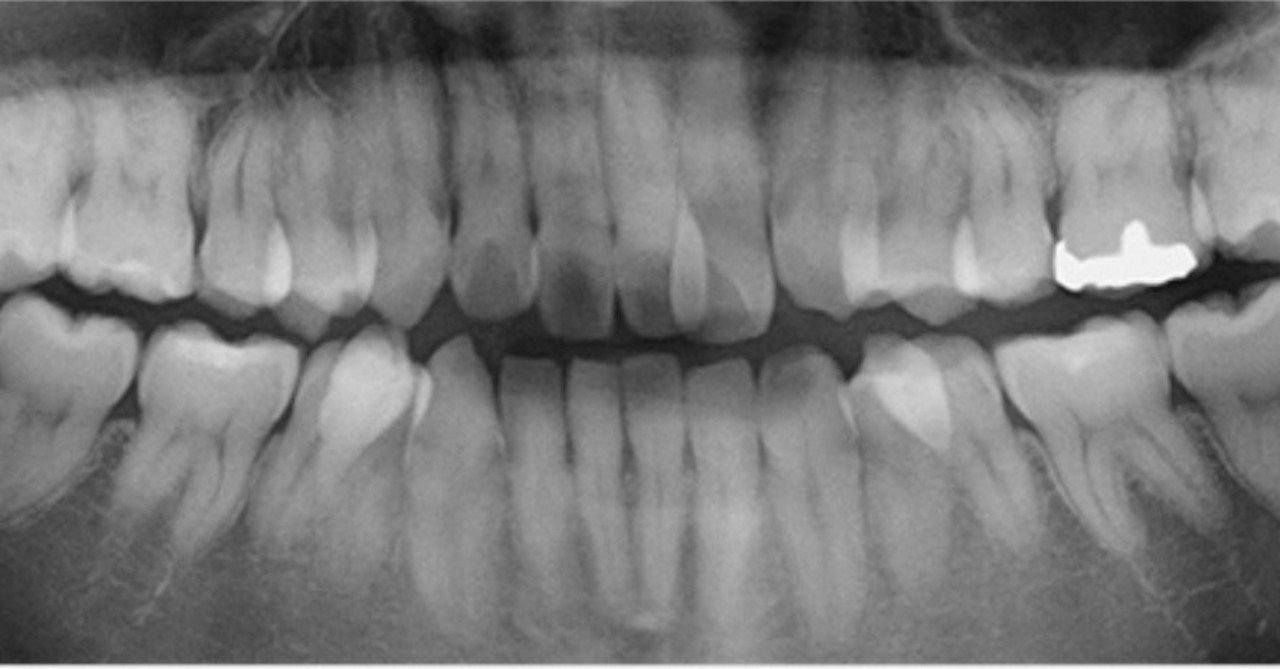

どうして歯が緩むの? 30歳以上になると、次のような変化が口の中に起こり歯に物が詰まりやすくなることがあります。 歯の移動 咬み合わせの力などによって、歯が移動して歯と歯の間の隙間が拡がりやすく、緩むため物が詰まりやすくなることがあります。 歯茎が下がる 歯周病などが原因で、以前より歯茎が下がった場所があると、歯と歯の境目を封鎖してい 治療後の被せ物から嫌な臭いがする原因とは? 「なんとなく口臭が気になる」治療をしたはずの歯の被せ物から、なんとなく嫌な臭いがする。 それは、気のせいではないかもしれません! では、その原因とは一体なんなのでしょうか? いくつか考えまずは、 クリーニング して、挟まった異物をすべてきれいに取り除き、洗浄、消毒し、むし歯の治療をし、食べ物が入り込んで歯ぐきを痛めている状態を改善させました。 神経まで達していないむし歯でしたので、神経は保存し、白い詰め物で治しました。 歯と歯の間の虫歯を放置すると、虫歯が進むだけでなく、つまったままの食べ物により歯茎が悪くなり

歯と歯の間に虫歯ができている、歯周病になっている、歯が動いている、食べ物が詰まりやすくなる原因は様々です。 食後にいつも同じところが詰まる場合は、何らかの問題を抱えており処置が必要な場合が ほとんどです。 当院は食べ物が詰まりにくい環境を重要視し、定期的な